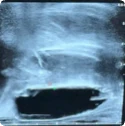

Salvage Placement & Separation

Procedural scan showing placement of the BioProtect Balloon Spacer in a salvage case. Saggital view.

Saggital Ultrasound

Image courtesy of Dr. Neil Wijetunga, Radiation Oncologist.